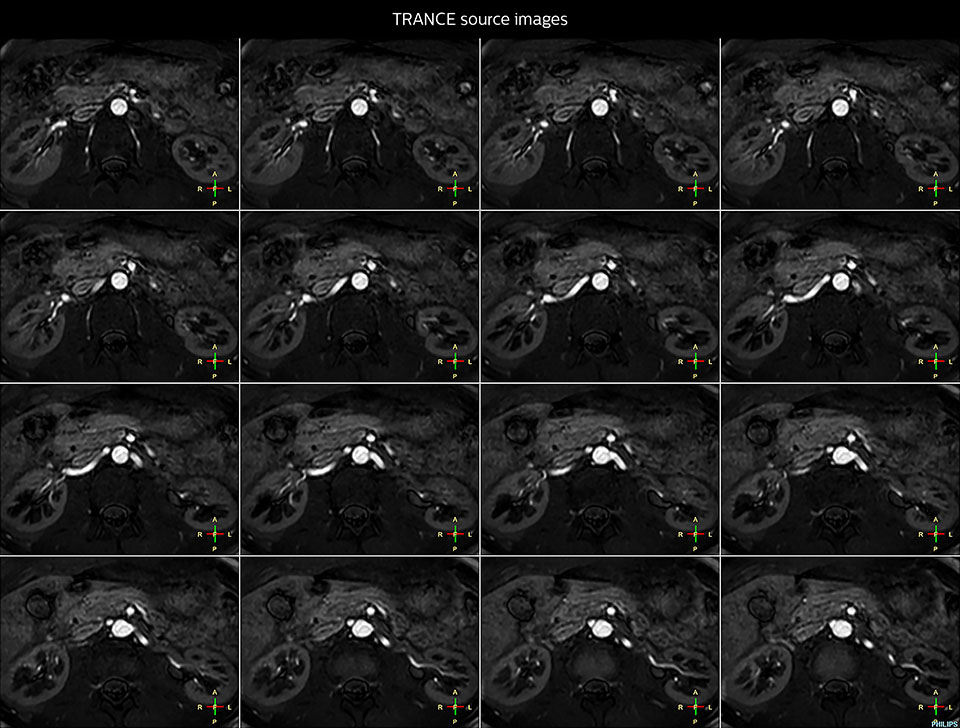

MRI of Pancoast tumor

Although the area between the neck and the top of the lung is one of the most difficult areas for MRI, Prodiva 1.5T images show good quality in this 56-year-old male with Pancoast tumor on the right. mDIXON TFE images shows excellent fat suppression in the neck area and the DWI shows almost no distortion.